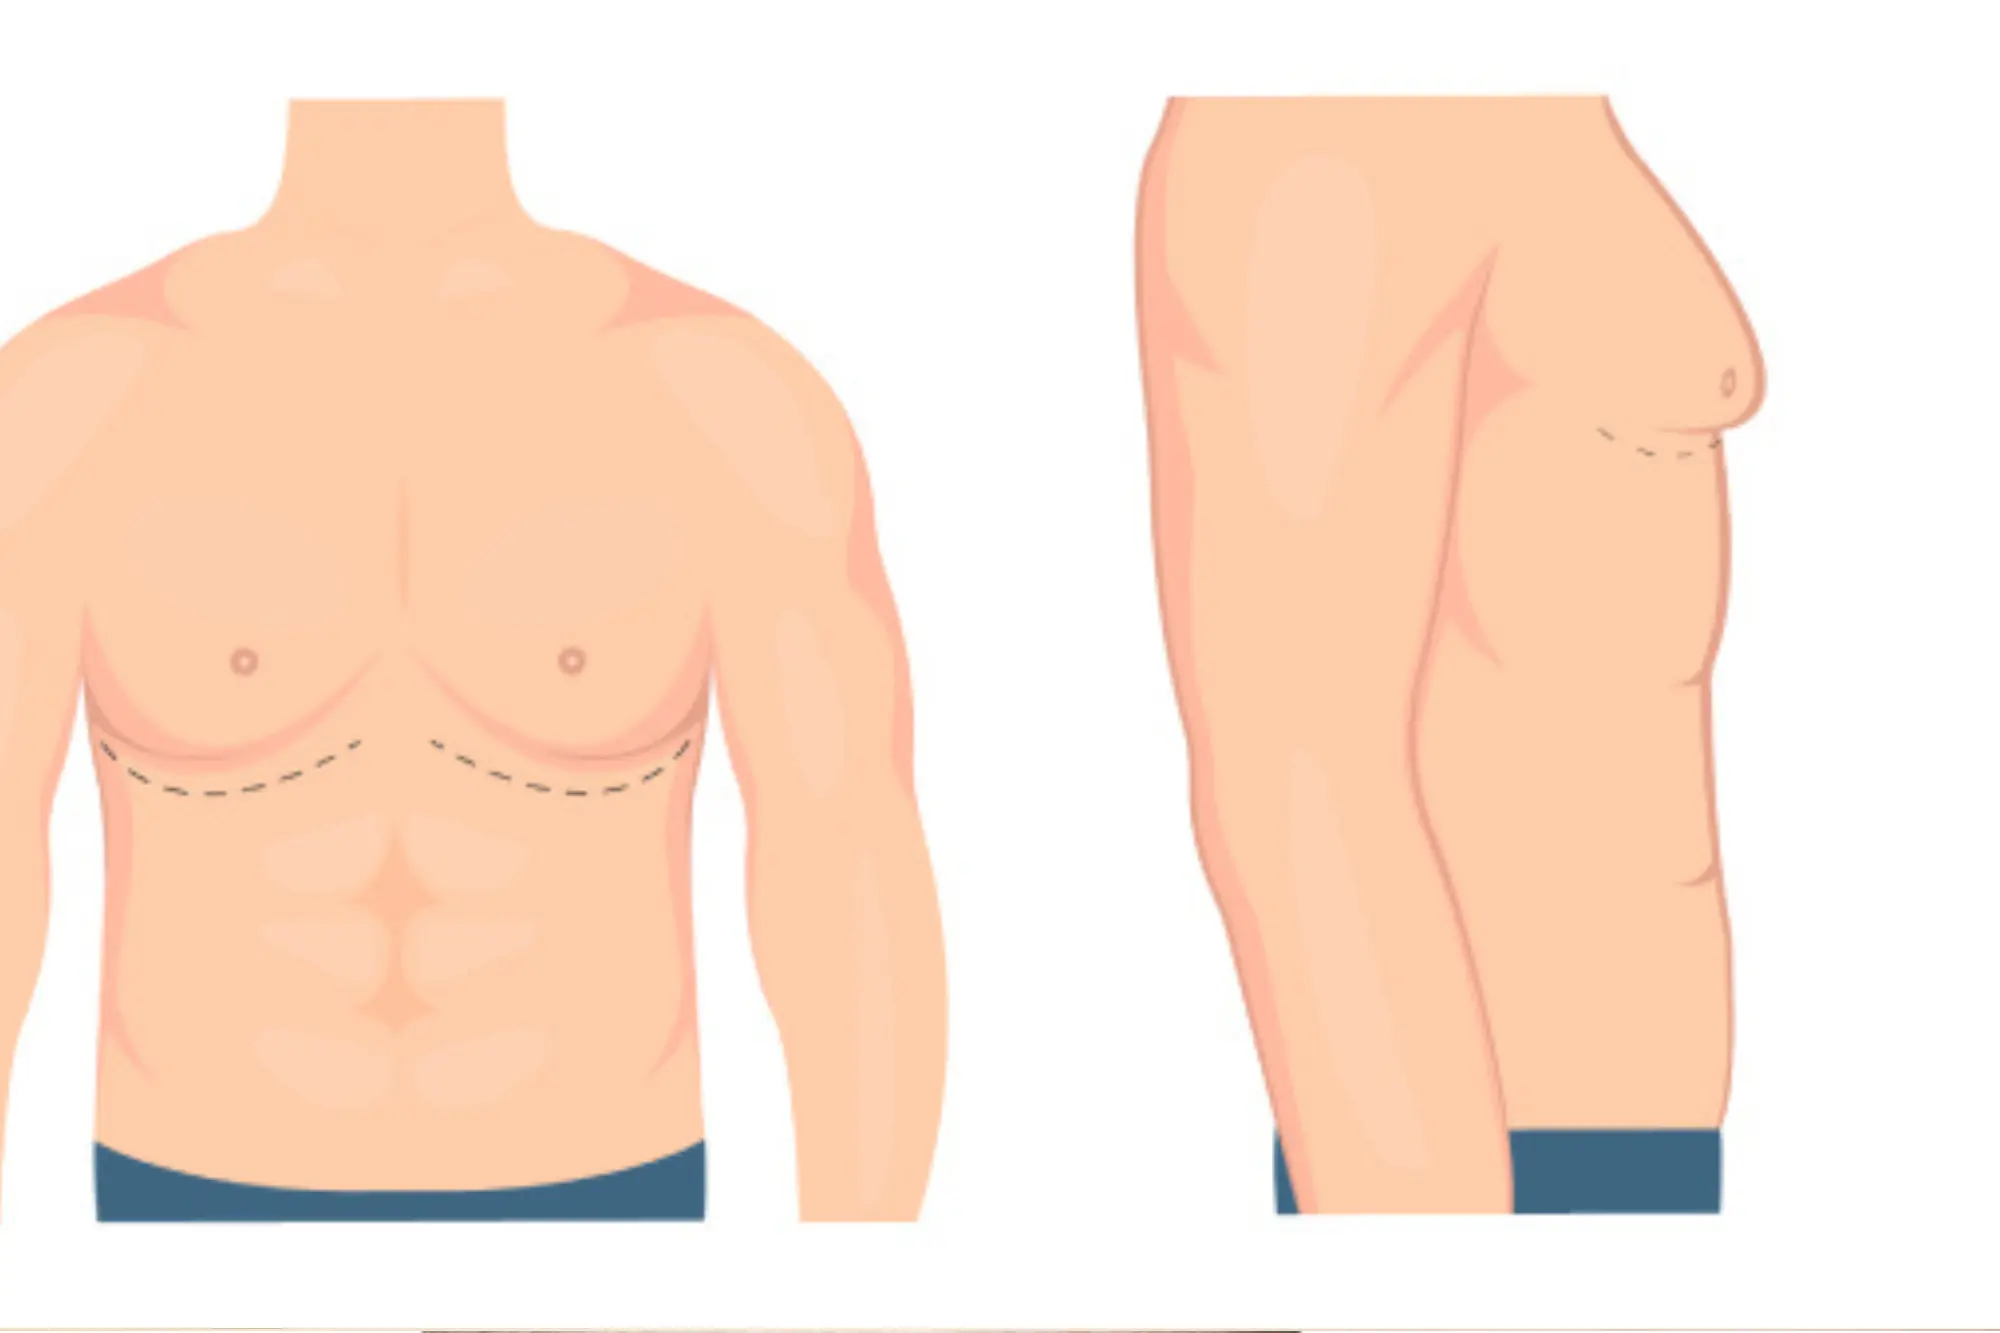

Aesthetic Gymnecomastia

Gynecomastia is the enlargement of male breast tissue, often causing discomfort or self-consciousness.